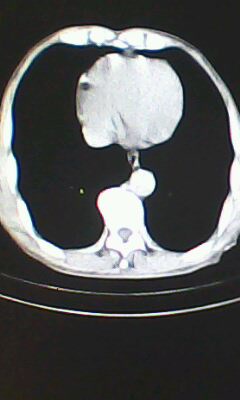

胸廓呈桶状,双膈低平,肺实质及纵隔未见明显异常密度灶考虑肺气肿.

胰尾部占位?

未见明显异常。“胰尾占位”为肠管

肺气肿

弥漫性肺气肿 但内胆管轻度扩张